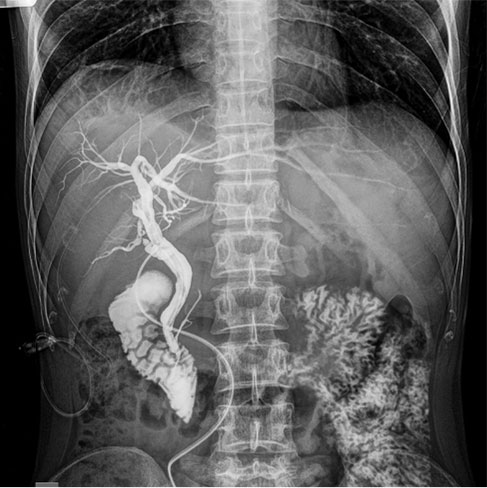

They are a series of radiographs of the gastrointestinal track obtained using Barium as the dye or contrast. Barium X-rays (also called upper and lower GI series) are used to diagnose abnormalities of the GI tract, such as tumours, ulcers and other inflammatory conditions, polyps, hernias, and strictures.

There are three types of barium X-ray procedures:

• Barium enema (also called lower GI series)

• Barium small-bowel follows through

• Barium swallow (also called upper GI series)